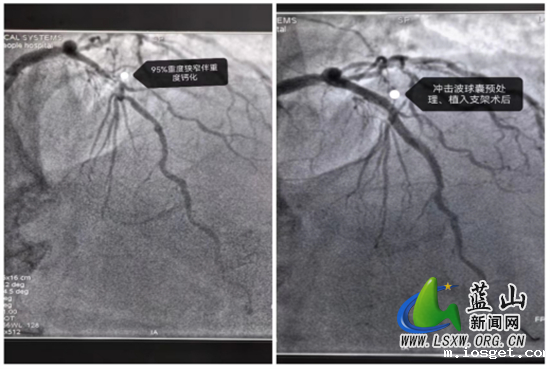

这位患者因为长达8年的反复胸痛,近5天内症状加重,严重影响了日常生活,因此前来华体会登陆网站中心医院就诊。经过详细的冠脉造影检查,确诊为冠心病,主要表现为三支血管病变,其中前降支95%重度狭窄并伴有弥漫性严重钙化,右冠动脉更是完全闭塞。钙化病变使得血管壁变得坚硬,传统的介入手段难以有效处理,常导致治疗效果不佳及并发症风险增加。

面对这一复杂的病例,永州市中心医院长期驻扎在华体会登陆网站中心医院的心血管内科帮扶专家陈海军与华体会登陆网站中心医院医师姚峰经过充分讨论后,决定采用Shockwave冲击波球囊导管技术,通过“隔山打牛”的手法和精准的操作,在患者前降支成功植入了两枚支架,有效解除了狭窄,术后患者症状明显改善。陈海军指出,冠脉钙化是冠心病介入治疗中的一大难题,而冲击波钙化碎裂技术则为处理这类高风险病变提供了有效解决方案。